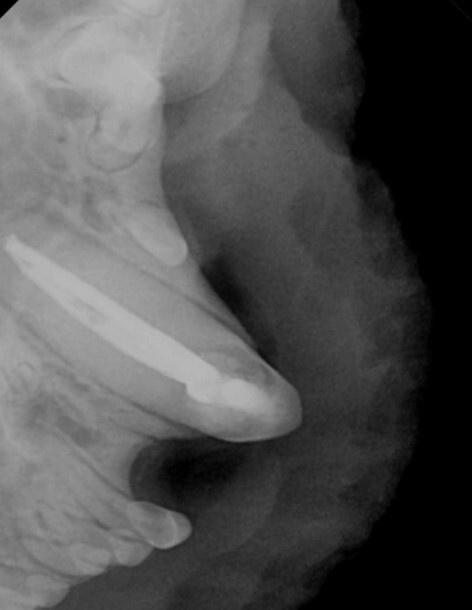

부러진 송곳니는 교정장치를 제거하면서 근관치료를

하고 1차 수술을 종료하였습니다.

며칠 후 교정장치 없이도 제 위치로의 교합을

확인한 후 근관치료를 진행하였습니다.